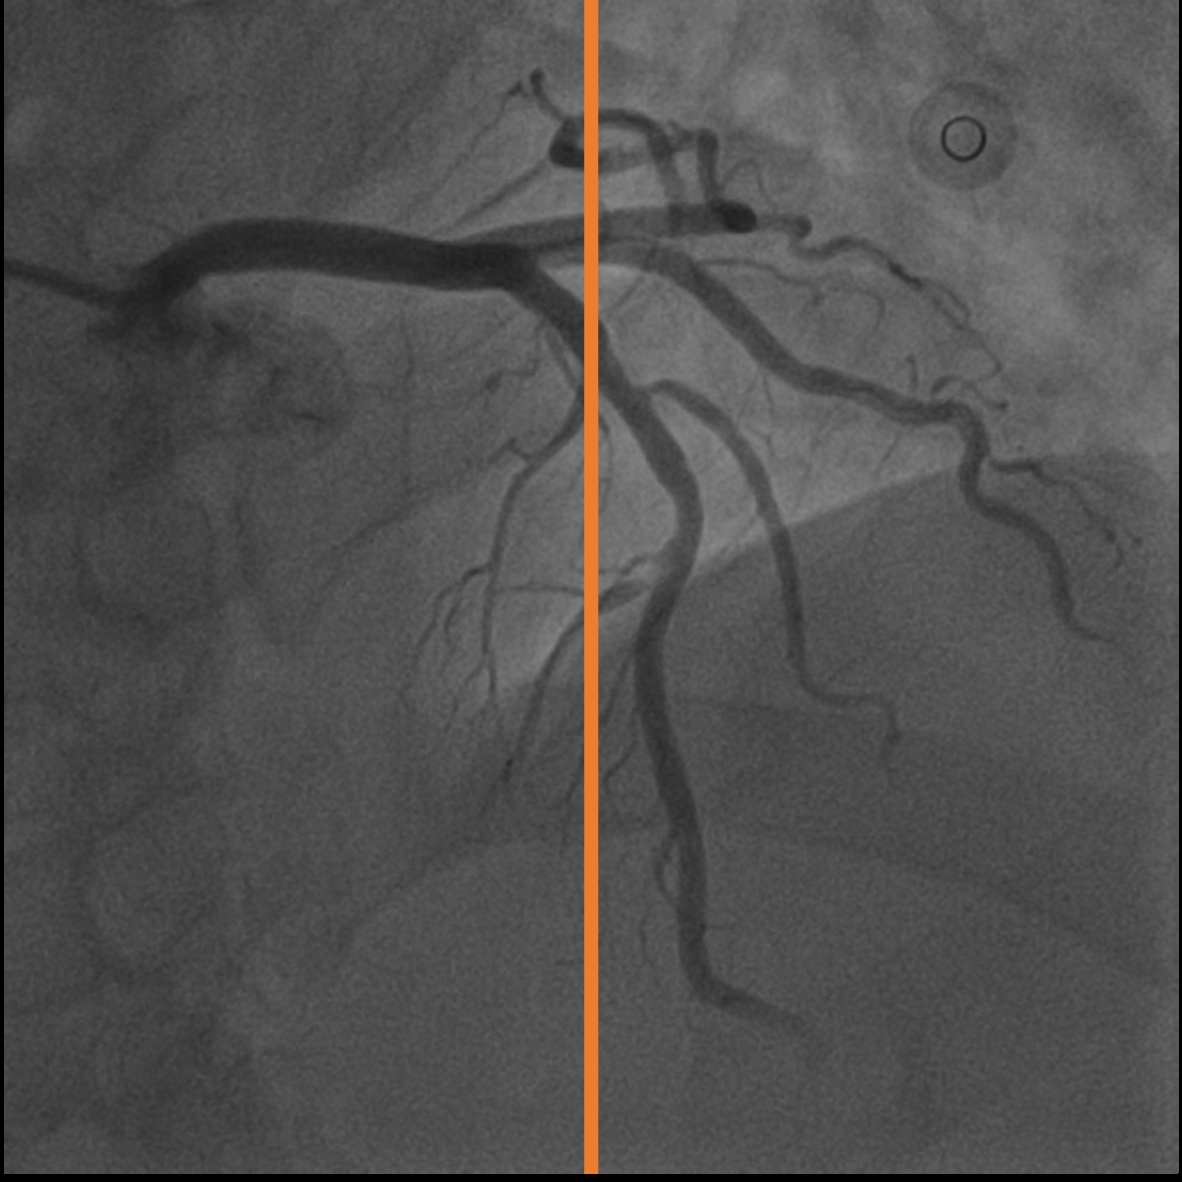

4.1 XACV Dataset

We collect 111 complete records of coronary artery X-ray videos, encompassing the injection, flow through the blood vessels around the heart, and dissipation of the contrast agent. Subsequently, we establish the XACV (X-ray Angiography Coronary Video) dataset. Each video consists of varying numbers of high-resolution coronary artery X-ray images. We invite experienced radiologists to annotate the vascular regions, focusing on one or two frames where the contrast agent is most prominent in each video. The XCAD dataset contains only a single image, and the CADICA video dataset does not provide corresponding ground truth. Therefore, in the following experiments, we conduct all the analyses on our collected XACV dataset and the corresponding GT for each sequence. In Figure 5, we show that compared to other publicly available datasets, XCAD [33] and CADICA [19], our dataset exhibits finer annotations in the vascular regions, providing an advantage for future related tasks. The development and use of our dataset have been approved by our institution’s IRB.